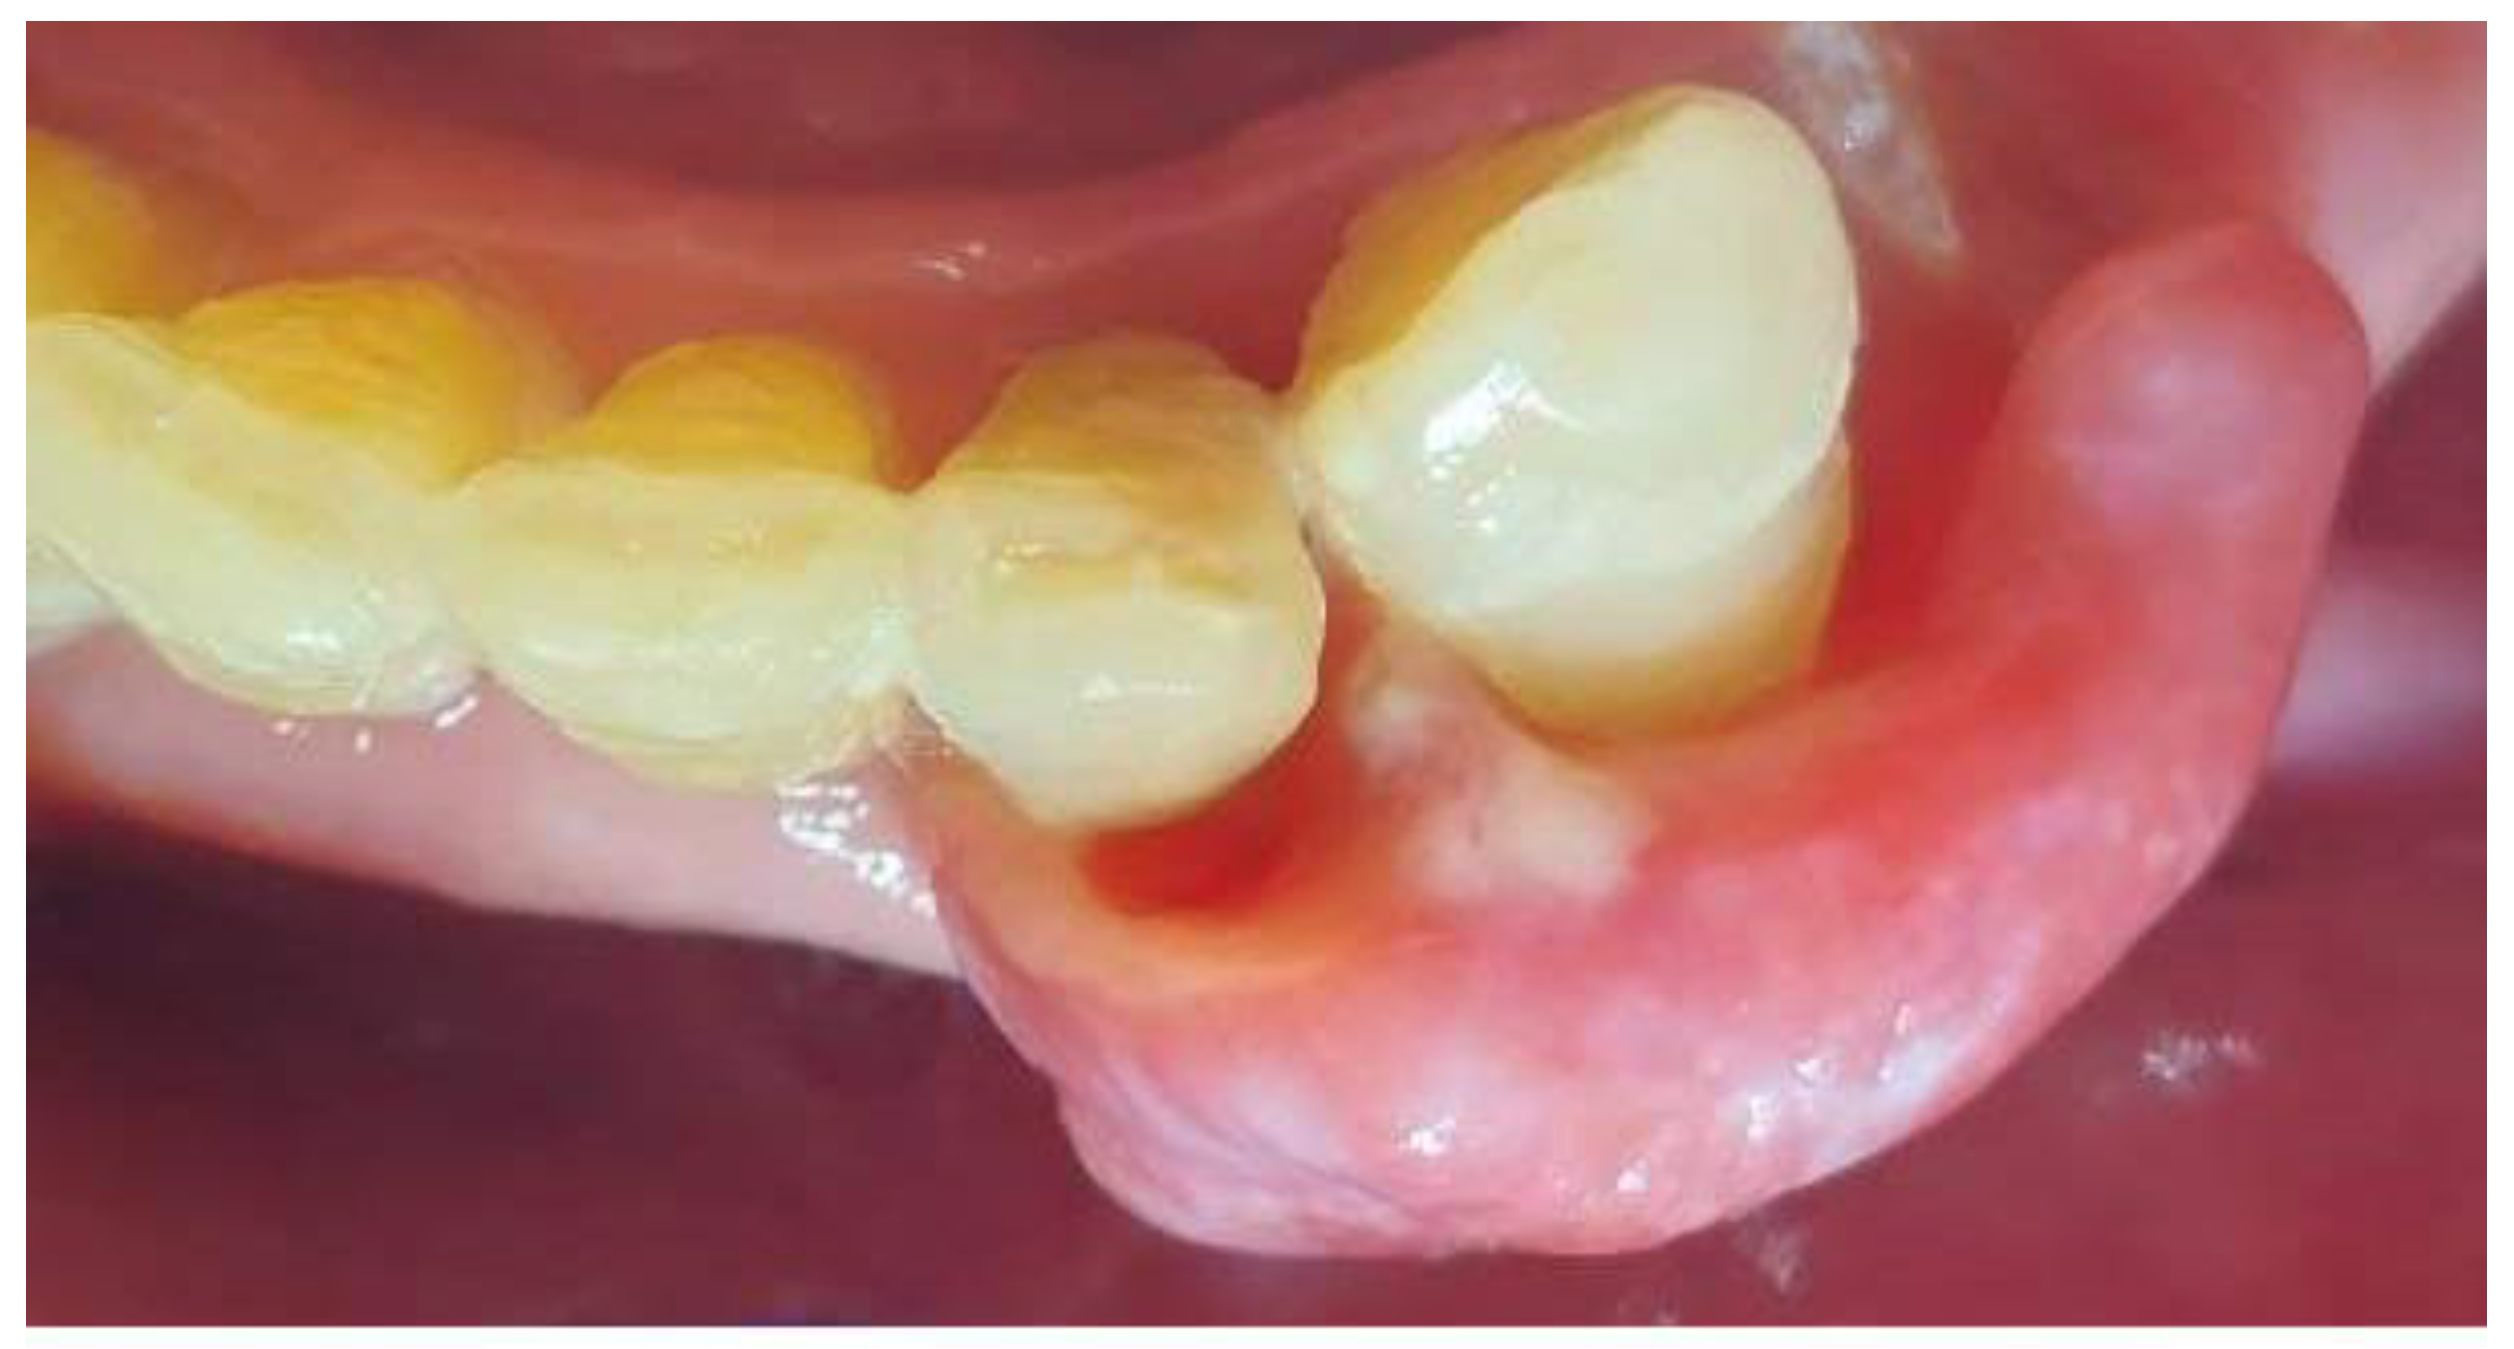

On the day of presentation to the Department of Oral Surgery, extraoral examination revealed painless, enlarged left submandibular lymph nodes. Intraorally, tumor-like gingival proliferations were observed in the regions of teeth 17–16 (22 × 10 × 5 mm) (Figure 1a) and 32–33 (30 × 20 × 6 mm), length, width, and thickness, respectively (Figure 2 and Figure 3). The lesions were pedunculated, elastic-hard, irregularly elliptical, and pink with areas of hyperemia and white spots. Both originated from marginal gingiva and were in close proximity to teeth. The patient also exhibited generalized periodontal disease with grade II mobility of teeth 17, 16, and 33. Residual roots of teeth 34, 35 were present. A panoramic radiograph showed no bony abnormalities. At this stage, the clinical appearance of the gingival lesions was suggestive of reactive hyperplastic conditions such as fibrous hyperplasia or pyogenic granuloma. However, these were considered only preliminary differential diagnoses, with the final diagnosis dependent on histopathological evaluation. The patient provided informed written consent for the proposed treatment.

Figure 2. Mandibular tumor in the area of teeth 32–33.

Figure 3. Mandibular tumor in the area of teeth 32–33.